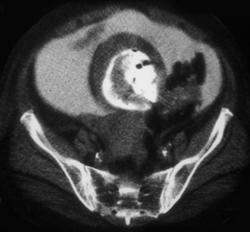

Right Adrenal Hematoma